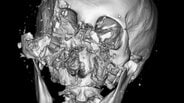

クマに襲われた患者のCT画像では、顔の骨が激しく砕けているのが分かります。